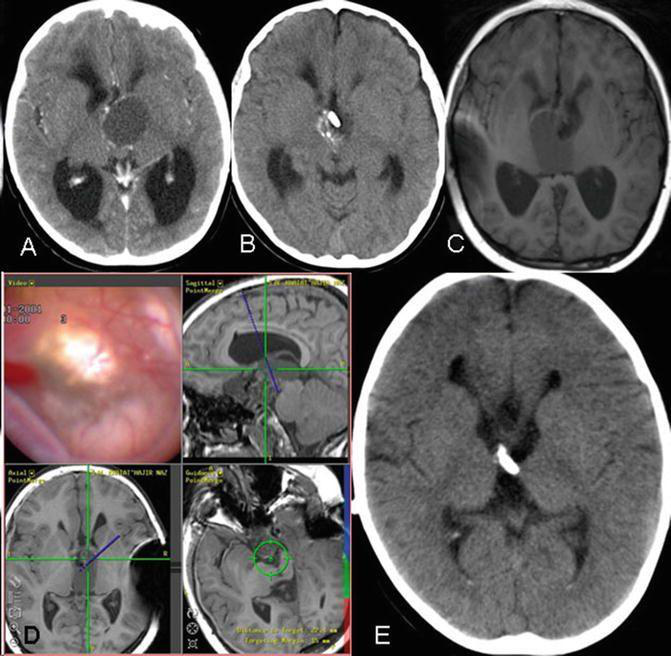

临床上可将颅咽管瘤分为六个类型:即鞍内型、鞍内鞍上型、鞍上脑室外型、脑室内外型、脑室旁型、单纯三脑室内型。通过分型可以简单判定手术入路的选择。但由于颅咽管瘤比邻重要的神经及血管,因此以往的专家认为手术难度较大,术后下丘脑损伤的几率很高。与此同时,肿瘤往往与周围组织结构粘连重,伴钙化,所以在内镜技术发展之前肿瘤全切率低,复发率较高,术后并发症多且复杂,患者生活质量低。

近几年的时间,神经内镜在外科治疗上的运用越来越广泛,技术的发展随之加速,神经内镜经鼻手术更是在颅咽管瘤的治疗上发挥重要作用。由于内镜可以通过鼻内入路更好的接触肿瘤,能够利用清晰的视野来明确肿瘤的构造,合适的辨别肿瘤是否和重要的神经相关联。并且通过微创技术将肿瘤较大水平额切除下来,做到更完全和更小损伤,明显的降低了术后并发症,提升了预后的效果。相关阅读:神经内镜下经鼻蝶手术的历史与演变

在《Craniopharyngioma: neuroendoscopic transnasal surgery》中报道2000年至2016年研究学者对92例颅咽管瘤患者进行内镜经鼻手术治疗,总共进行了125次手术,表示尿崩症是61%的患者术后常见的并发症,但通过对内镜经鼻手术的患者在1年的随访中只有2例患者出现持续性尿崩症。

与此同时Fahlbusch等报道了168例颅咽管瘤患者14年来的手术治疗。经颅和经鼻切除肿瘤的比例分别为45.7%和85.7%,经鼻全切后5年的存活率是86.9%,10年的为81.3%。部分切除后5年存活率为48.8%,10年存活率为41.5%。在3年的回访期间,颅咽管瘤的死亡率和发病率分别为5%和22.2%。